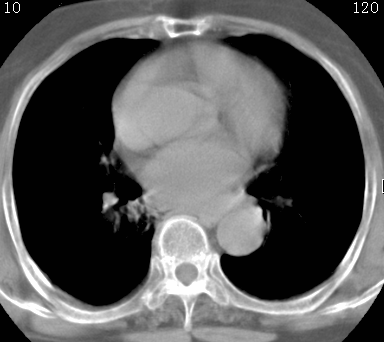

标题: CT26680:肺部右下肺静脉干结节的界定 [打印本页]

标题: CT26680:肺部右下肺静脉干结节的界定

经追查说有支扩咯血病史,但不确定

考虑1、周围型肺癌,2肺静脉畸形,前者可能大,建议增强检查。

考虑1、周围型肺癌,2肺静脉畸形,前者可能大,建议增强检查。支持!

不排除右肺下叶周围型肺癌可能。

中心型肺癌,纤支镜可帮助明确。